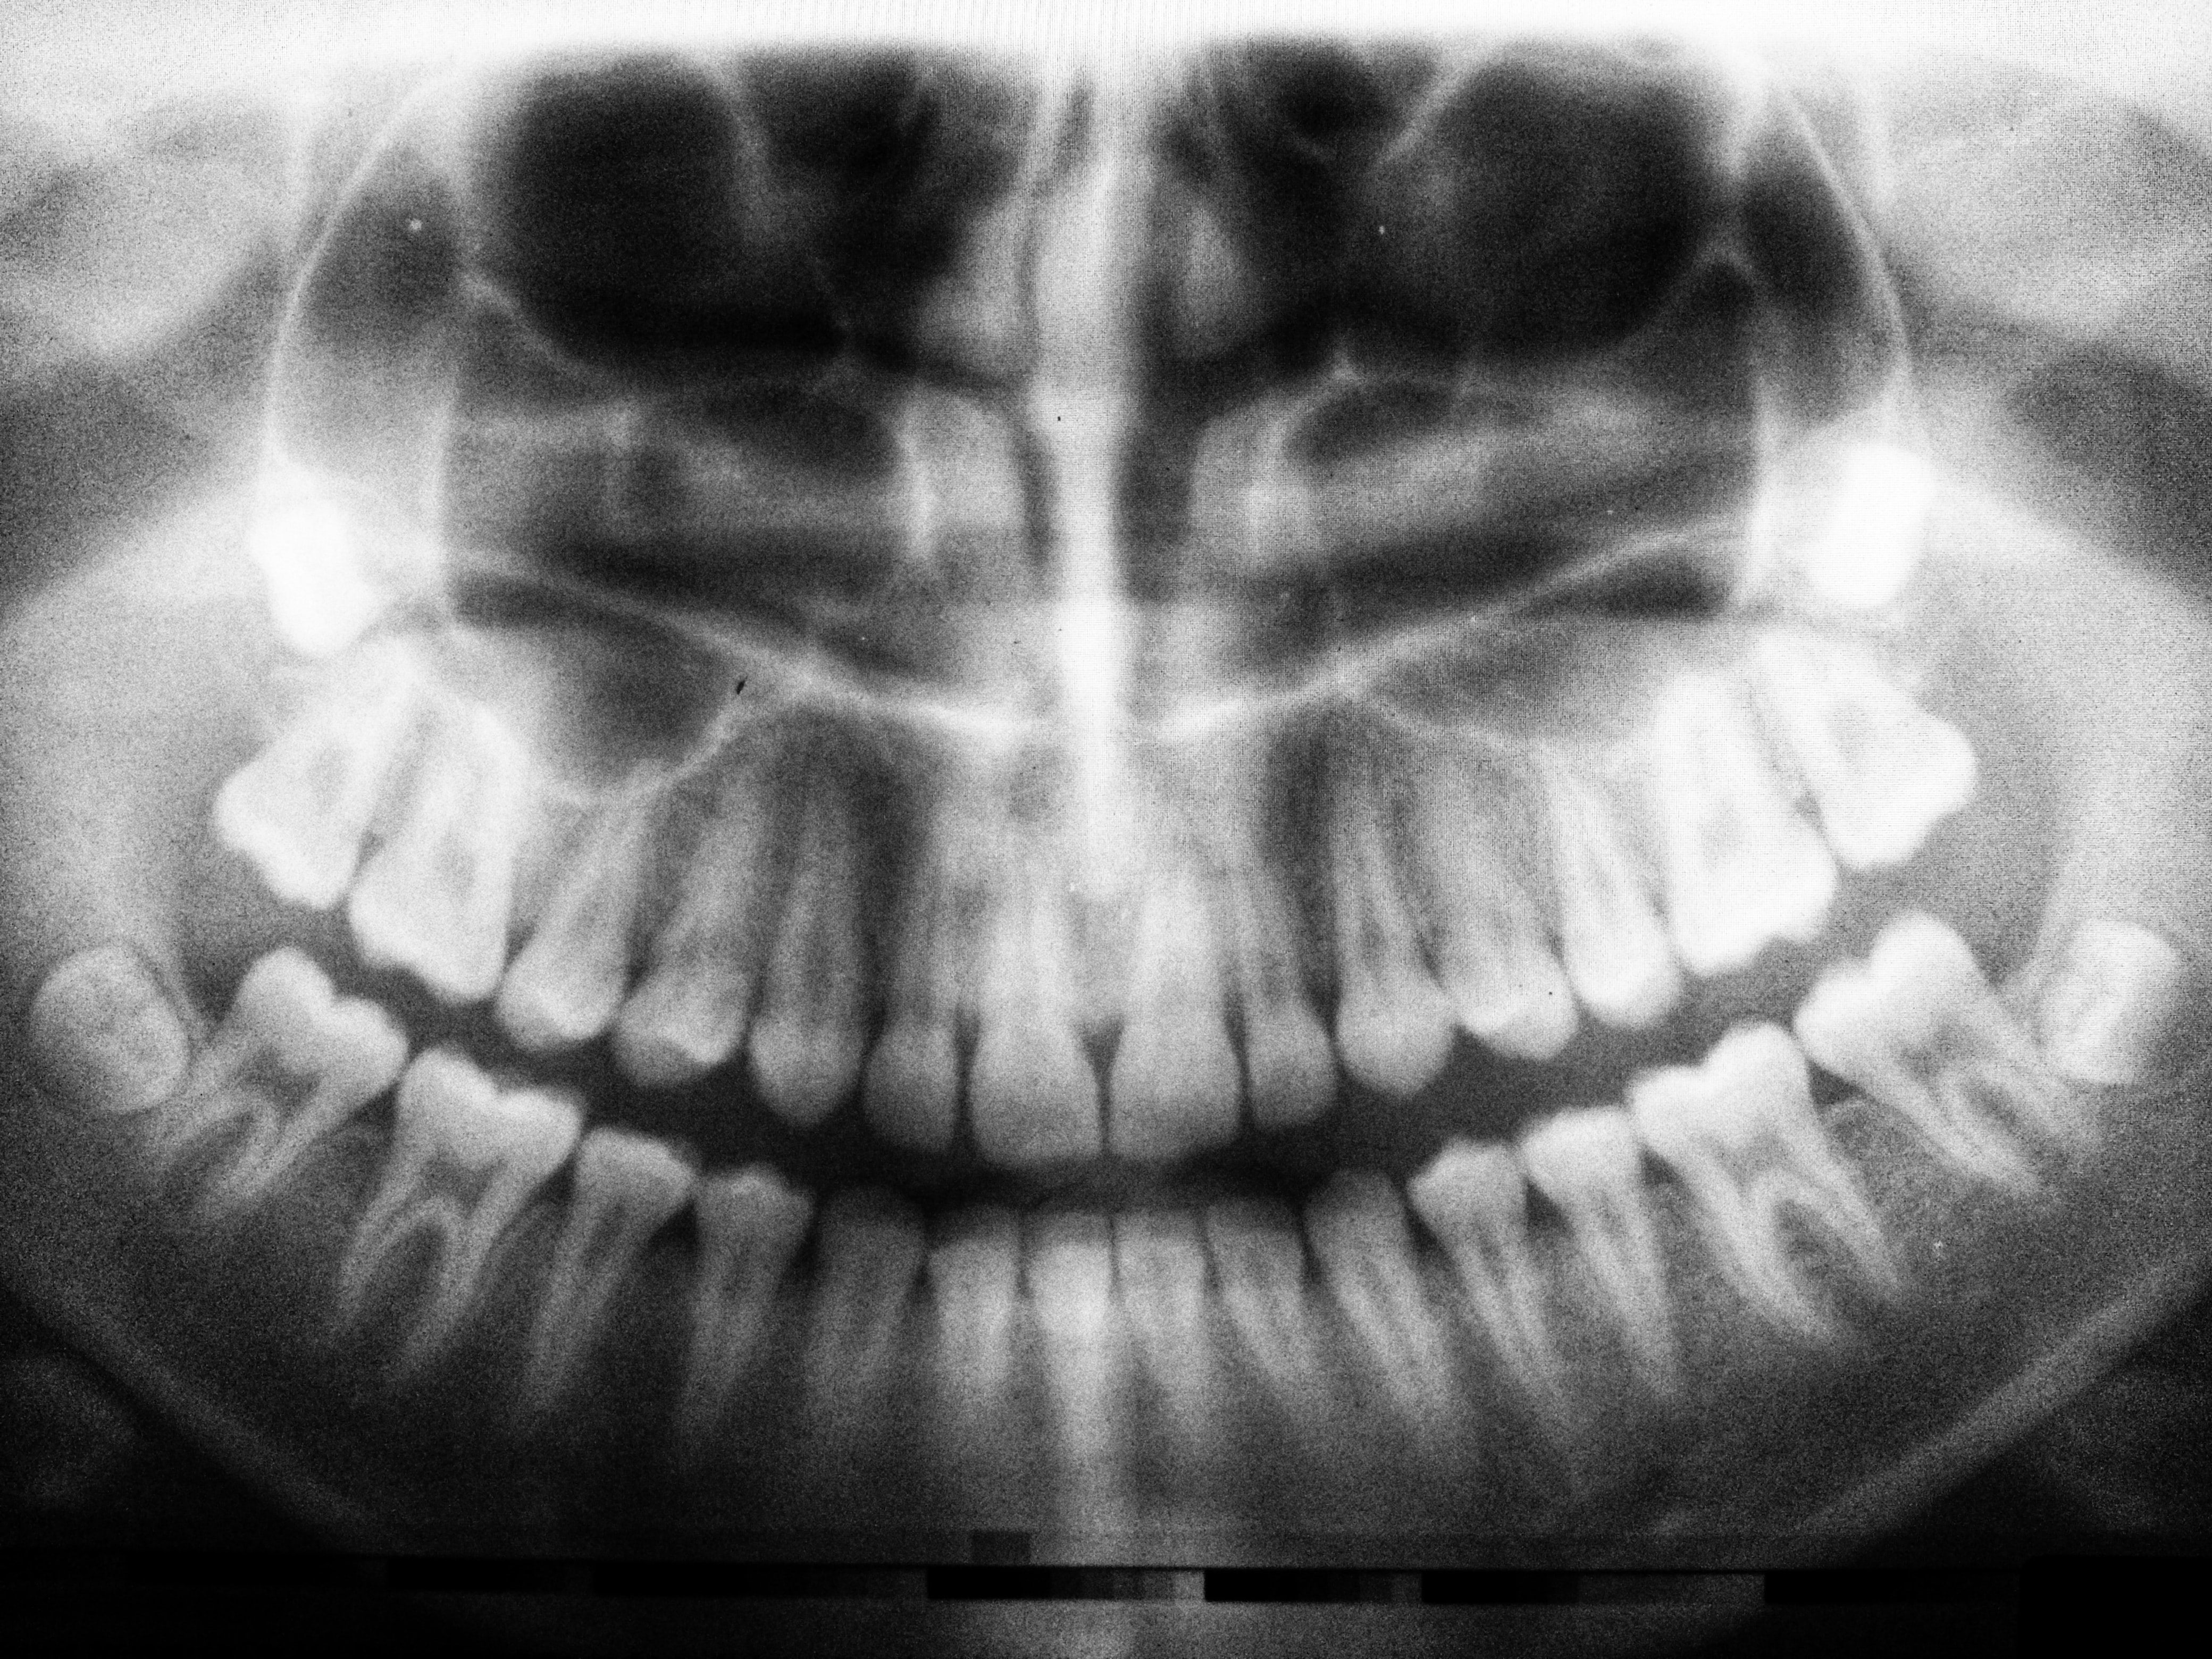

As an astute artist, Mr. Catlin was also extremely observant and gave great attention to detail. As a result, he noticed a common theme among all the indigenous peoples that he met: most all of them had perfect airways. Their faces were large, strong, symmetrical-beautiful. They had prominent cheekbones and strong lower jaws, as well as large nasal passages. Their smiles were wide and not only did they have all their teeth (wisdom teeth included), but there was room for them as well. They were not crowded. They were fit, had energy, and did not suffer from allergies and many of the ailments that were common among his peers in the Eastern United States.